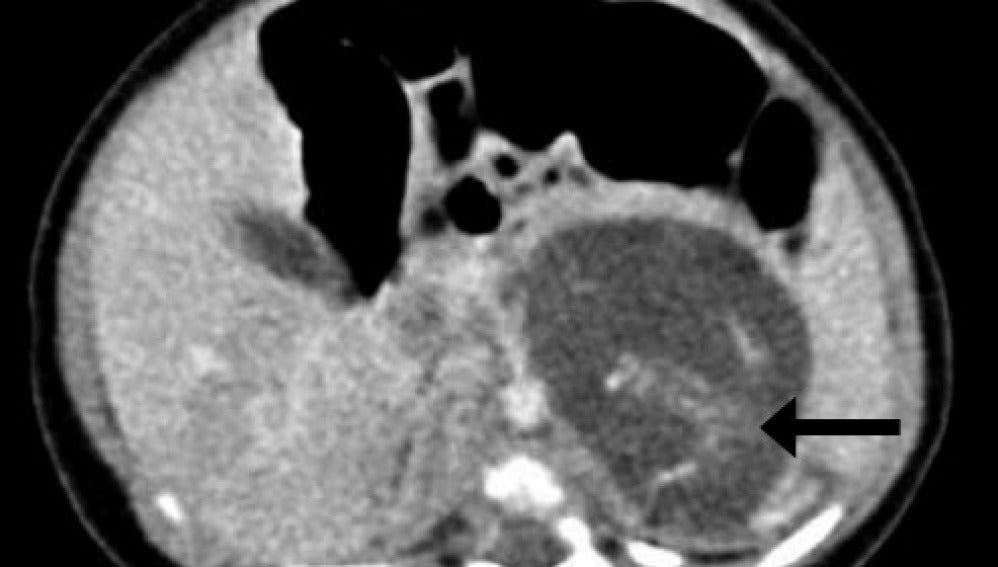

Tomografia computarizada mostrando la espina dorsal de uno de los dos "fetos" Hong Kong Med Journal

Cada “feto” tenía cuatro extremidades, piel, una caja torácica, los intestinos y un tejido cerebral primitivo. Ambos estaban unidos por un cordón umbilical, según describen los especialistas que atendieron atónitos al parto, que tuvo lugar en 2010.

El estado de desarrollo de los fetos (o tumores) podría situarse entre las ocho y diez semanas de gestación, según los expertos. Tenían espinas dorsales, genitales externos ambiguos y aún no habían desarrollado el cráneo.